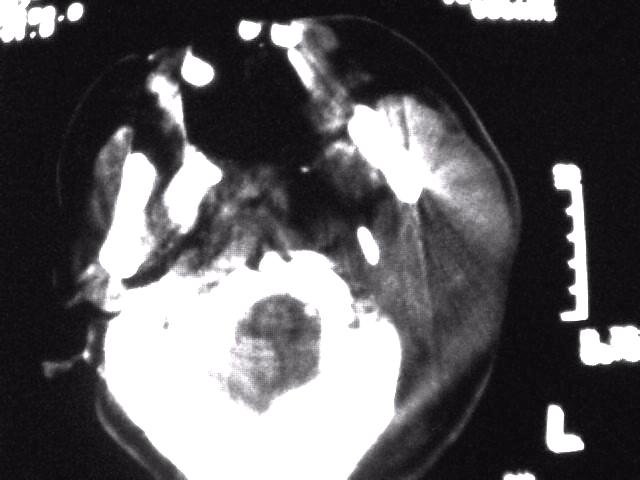

颈部层厚10mm间距10mm连续扫描及增强扫描共24层示:左侧下颈部胸锁乳突肌内侧区域内可见多发软组织结节,密度不均,内可见斑片状低密度区,大小不等,部分融合成块,左侧融合成一块者大约9.0x5.4,与周围肌肉、血管等结构界面不清,骨质未见明显浸润影。左侧锁骨下可见多个软组织结节,与周围界限尚清,左侧锁骨上窝内可见一大软组织肿物,大小约4.7x3.7cm,内密度欠均匀中心可见低密度区。

考虑:左侧颈部及双侧锁骨下多发淋巴结肿。非何杰金氏淋巴瘤可能性大,建议进一步检查。